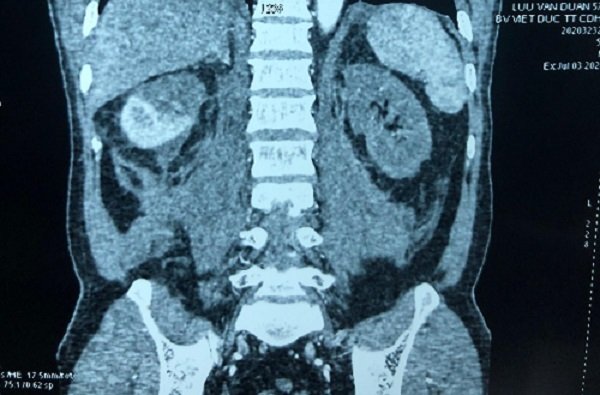

Mang thận ra rửa rồi ghép lại vào cơ thể bệnh nhân

Bệnh viện Hữu nghị Việt Đức cho biết, bệnh nhân được ghép thận tự thân do có biểu hiện suy thận sau ca tai nạn.